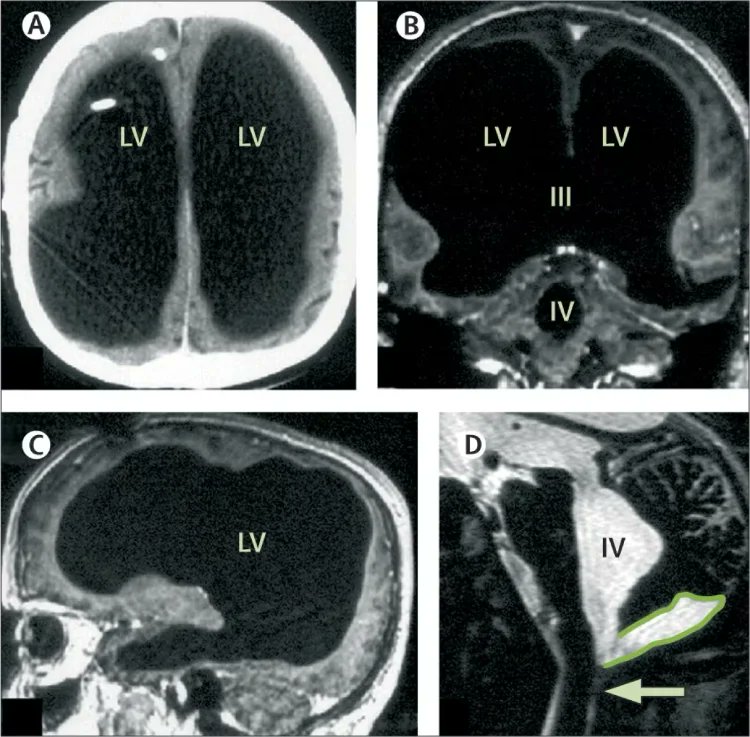

[في اليمين دماغ شخص طبيعي، في اليسار دماغ الرجل]

في أحد الأيام، بدأ يشتكي من ضعف بسيط في قدمه اليسرى، قرر الذهاب للطبيب، أجرى الأطباء سلسلة من الفحوصات، بما في ذلك تصوير للدماغ بالأشعة لاكتشاف سبب اعراضه، الذي ظهر في الشاشة صدم الفريق الطبي. كان امامهم فراغ كبير في رأسه.

اظهر الفحص شيئا استثنائيا: كانت جمجمته مليئة بالسائل النخاعي إلى حد كبير ولم يتبقى الا طبقة رقيقة فقط من نسيج الدماغ. تعرف هذه الحالة باسم الاستسقاء الدماغي او hydrocephalus

لكن مدى حالته غير مسبوق،كان فاقد لـ 90% من كتلة دماغه، بمعنى انه يعيش بـ 10% دماغ